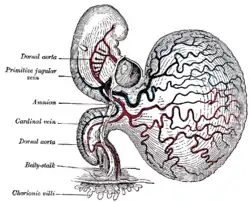

Micrograph showing chorionic villi. Very high magnification. H&E stain. Section through the embryo.

Transverse section of a chorionic villus. Human embryo of about 28 days, with yolk-sac.

Human embryo of about 28 days, with yolk-sac.